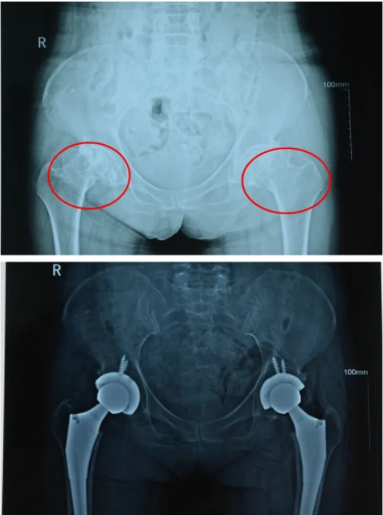

术前、术后摄片

近日,娄星区人民医院骨科/康复理疗中心收治了一位59岁的女性患者蔡阿姨(化名),14年前她出现双侧髋关节疼痛不适,近一年逐渐加重,并出现了双下肢跛行,经检查发现双侧股骨头坏死,必须行双侧髋关节置换术才能提高生活质量。前段时间,蔡阿姨的家人在娄星区人民医院的微信公众号上看到,骨科曾为一位贫困户患者做过同类型的一期双髋手术,手术非常成功,于是,他们慕名来到医院找到了骨科主任张勇。在全面了解蔡阿姨的病情后,经过严格术前讨论、手术计划、假体选择、围术期各种可能发生的情况作出预判和周密安排,医院精心组织全院多学科联合会诊,最终制定出详细的手术治疗和护理康复方案。

4月9日下午,在张勇主任的带领下,经过3个小时的紧张手术,蔡阿姨顺利从手术室返回病房,目前情况良好,后续的治疗、护理、康复正一步步跟进。

张勇主任表示:“在一期同时进行双侧髋关节置换术,不是1+1=2那么简单,它难度大、风险高,不仅需要我们多方配合,还需要有一个强大的团队,今后对这类高难度髋关节置换手术,我们不但能做,而且会做的越来越好。”手术完成当日,张勇在朋友圈表达自己作为医者矢志不渝的初心。

同时进行两个大关节置换与分次关节置换手术相比, 不但能减轻患者痛苦, 缩短了住院时间, 降低了手术费用, 还减少了患者术后康复时间。同时一期进行置换需要手术医师精湛医术和团队的默契配合,包括手术医生、麻醉医师、器械护士、病房护士及术后康复团队,各司其职,全力以赴,才能保证手术井然有序、安全顺利的完成。此项手术的成功进行,说明娄星区人民医院骨科业务能力平又提升了一个新的高度,再次增强了医院在骨科手术领域的核心竞争力。